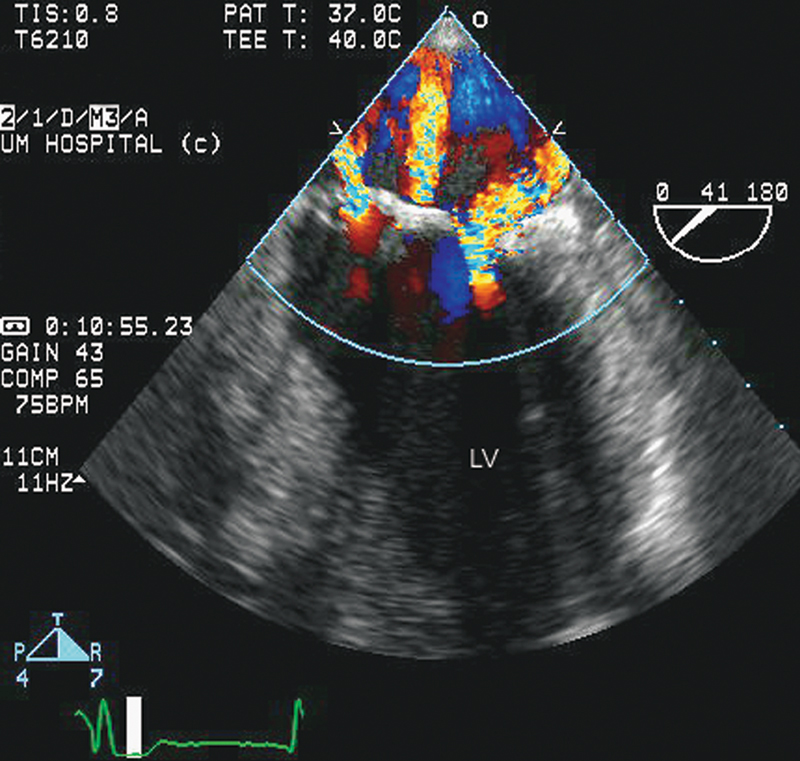

فحوصات تشخيصية لبعض امراض القلب والشرايين التاجية